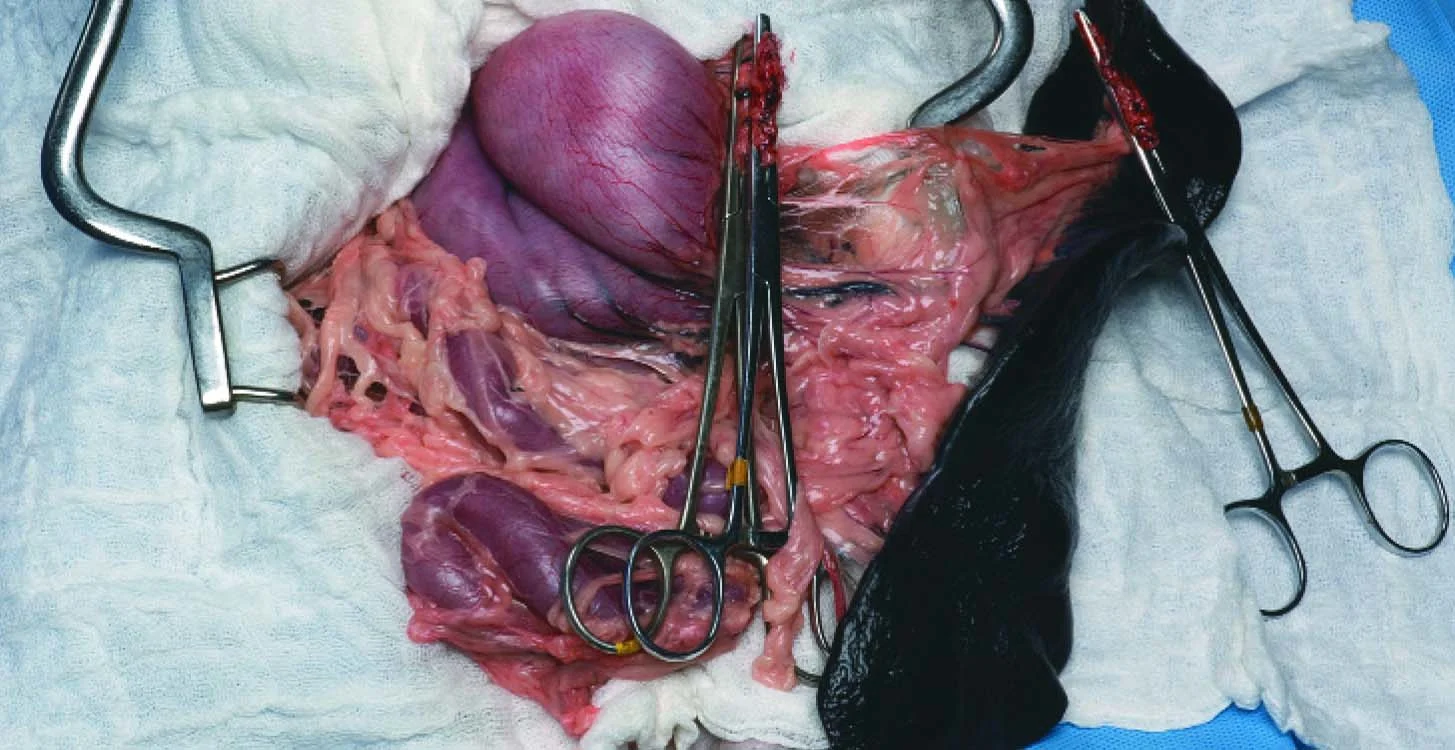

Step 9

Remove the spleen with the associated forceps still attached to the pedicles and submit for biopsy. The figure shows a completed splenectomy showing 4 clamped pedicles (forceps #3) on the spleen.

Torsion

Avoid the temptation to untwist the pedicle, even though it facilitates ligation of vessels to the spleen in cases of torsion (Figure 3). It can release thrombi and vasoactive compounds into the circulation, causing significant hemodynamic disturbance. Divide the distal pedicle into several en masse ligations, or attempt to partially untwist just enough of the pedicle distal to the pancreas to help isolate the main splenic vessel divisions for ligation. Once the pedicles have been clamped and the spleen removed, completely untwist the proximal aspect to release the pancreas. If the pancreas appears compromised, perform a partial pancreatectomy.